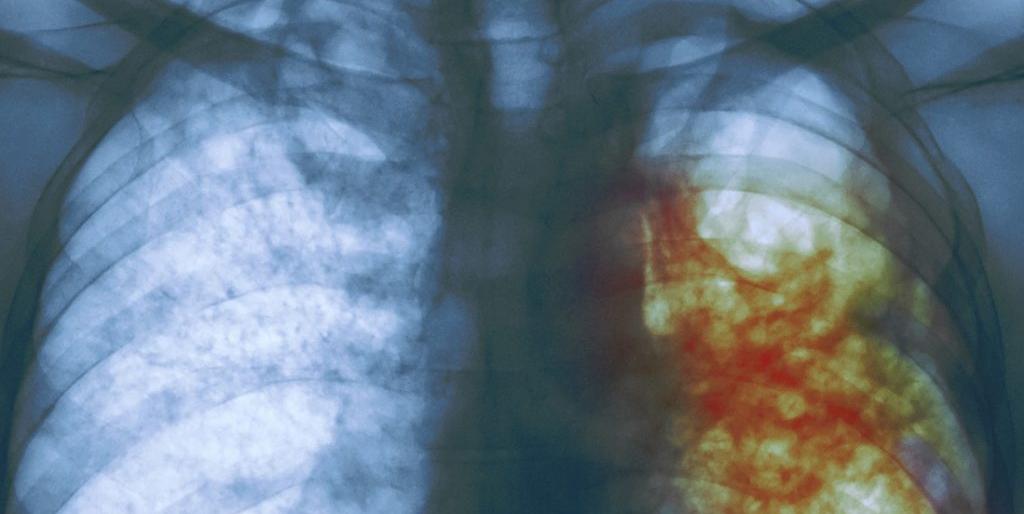

Как было установлено, диагностический рентгеновский комплекс тубдиспансера вышел из строя еще 1,5 года назад. Однако приводить в порядок его никто не спешил.

Прием пациентов тубдиспансера в районной больнице прекращен. А в самом диспансере запущен в работу портативный переносной малодозовый рентгенаппарат, который будет использоваться во время ремонта основного рентгеновского комплекса.